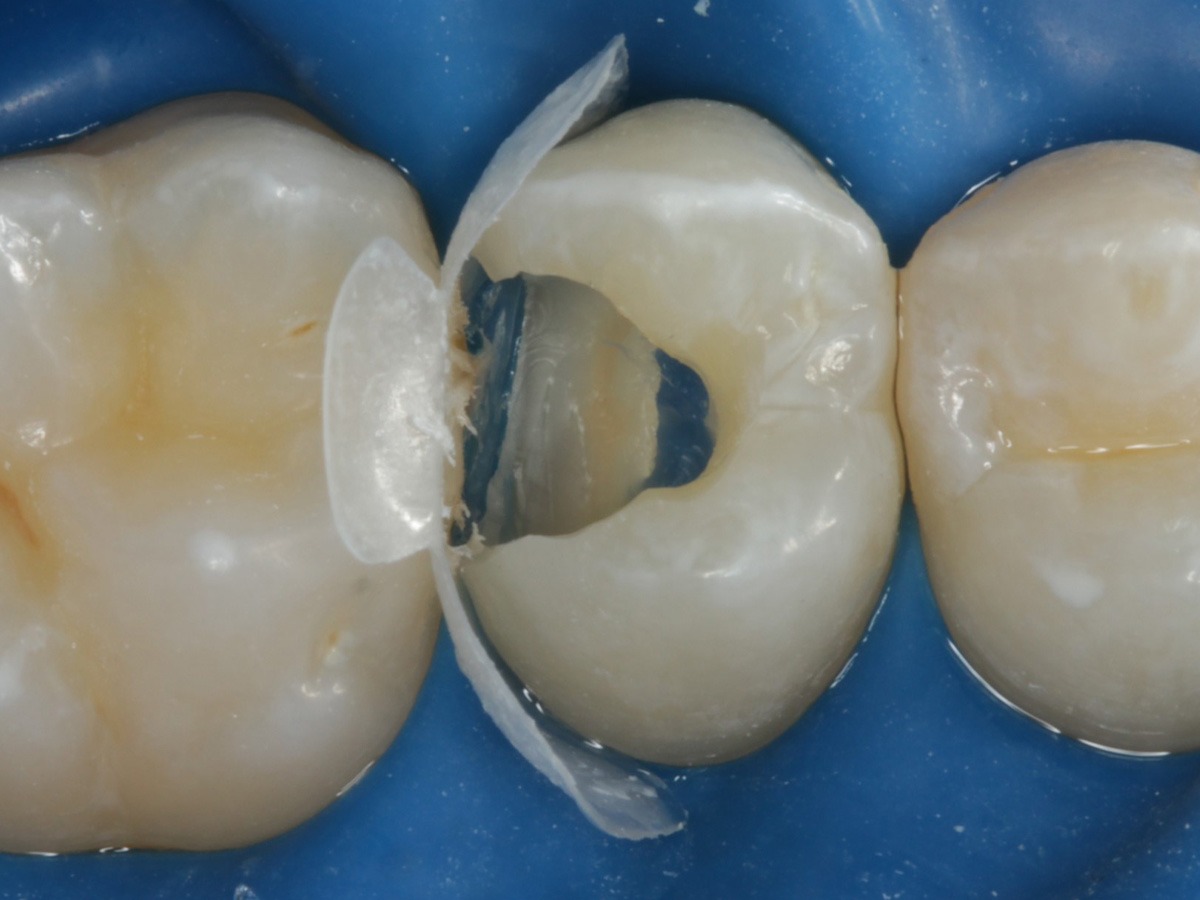

Abbildung 5

Height Indicator vor Auswahl der passenden Evolve Matrize nach Defektdarstellung, Kariesexcavation, Vitalexstirpation

Abbildung 6

Pulpenkavum mit Watte und farbigem Komposit abgedeckt; zuvor Spülung der Wurzelkanäle nur mit NaCl zwecks Nichtgefährdung der Kompositadhäsion